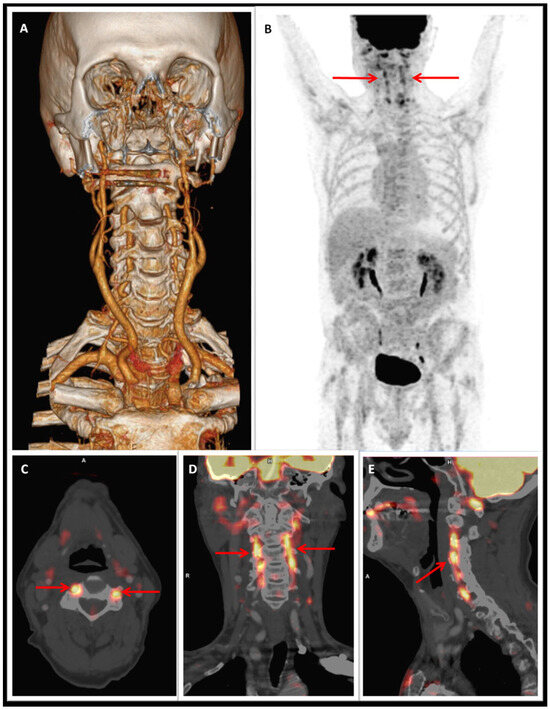

Ischaemic type ECG-modifications are not always correlated to cardiac causes. We present a case of a 63-yearold man with metastatic kidney carcinoma who had ECGabnormalities suspicious for myocardial ischaemia due to a biliary problem, which were com...